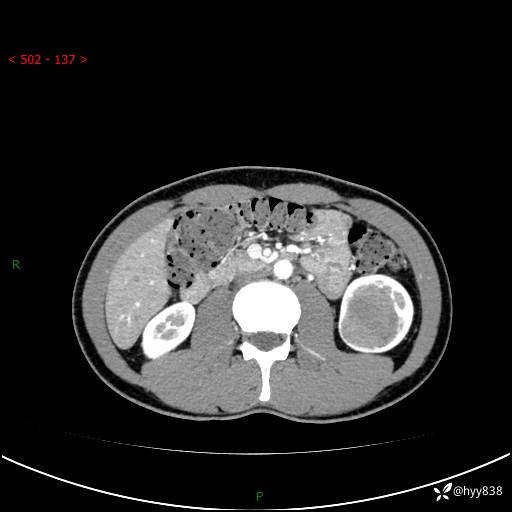

现病史:患者昨日中午进食后出现明显腹痛,腹泻,在我院急诊科行补液及对症治疗,双肾输尿管彩超提示左肾占位(5.2*4.3cm),平素无明显腰痛,无再发肉眼血尿等情况,现为求处理左肾占位,遂来我院,门诊以左肾占位收治入院。 患者起病以来,精神、食欲、睡眠尚可,大便可,小便如上,体力体重无明显下降。

双肾CT平扫+增强(三期)